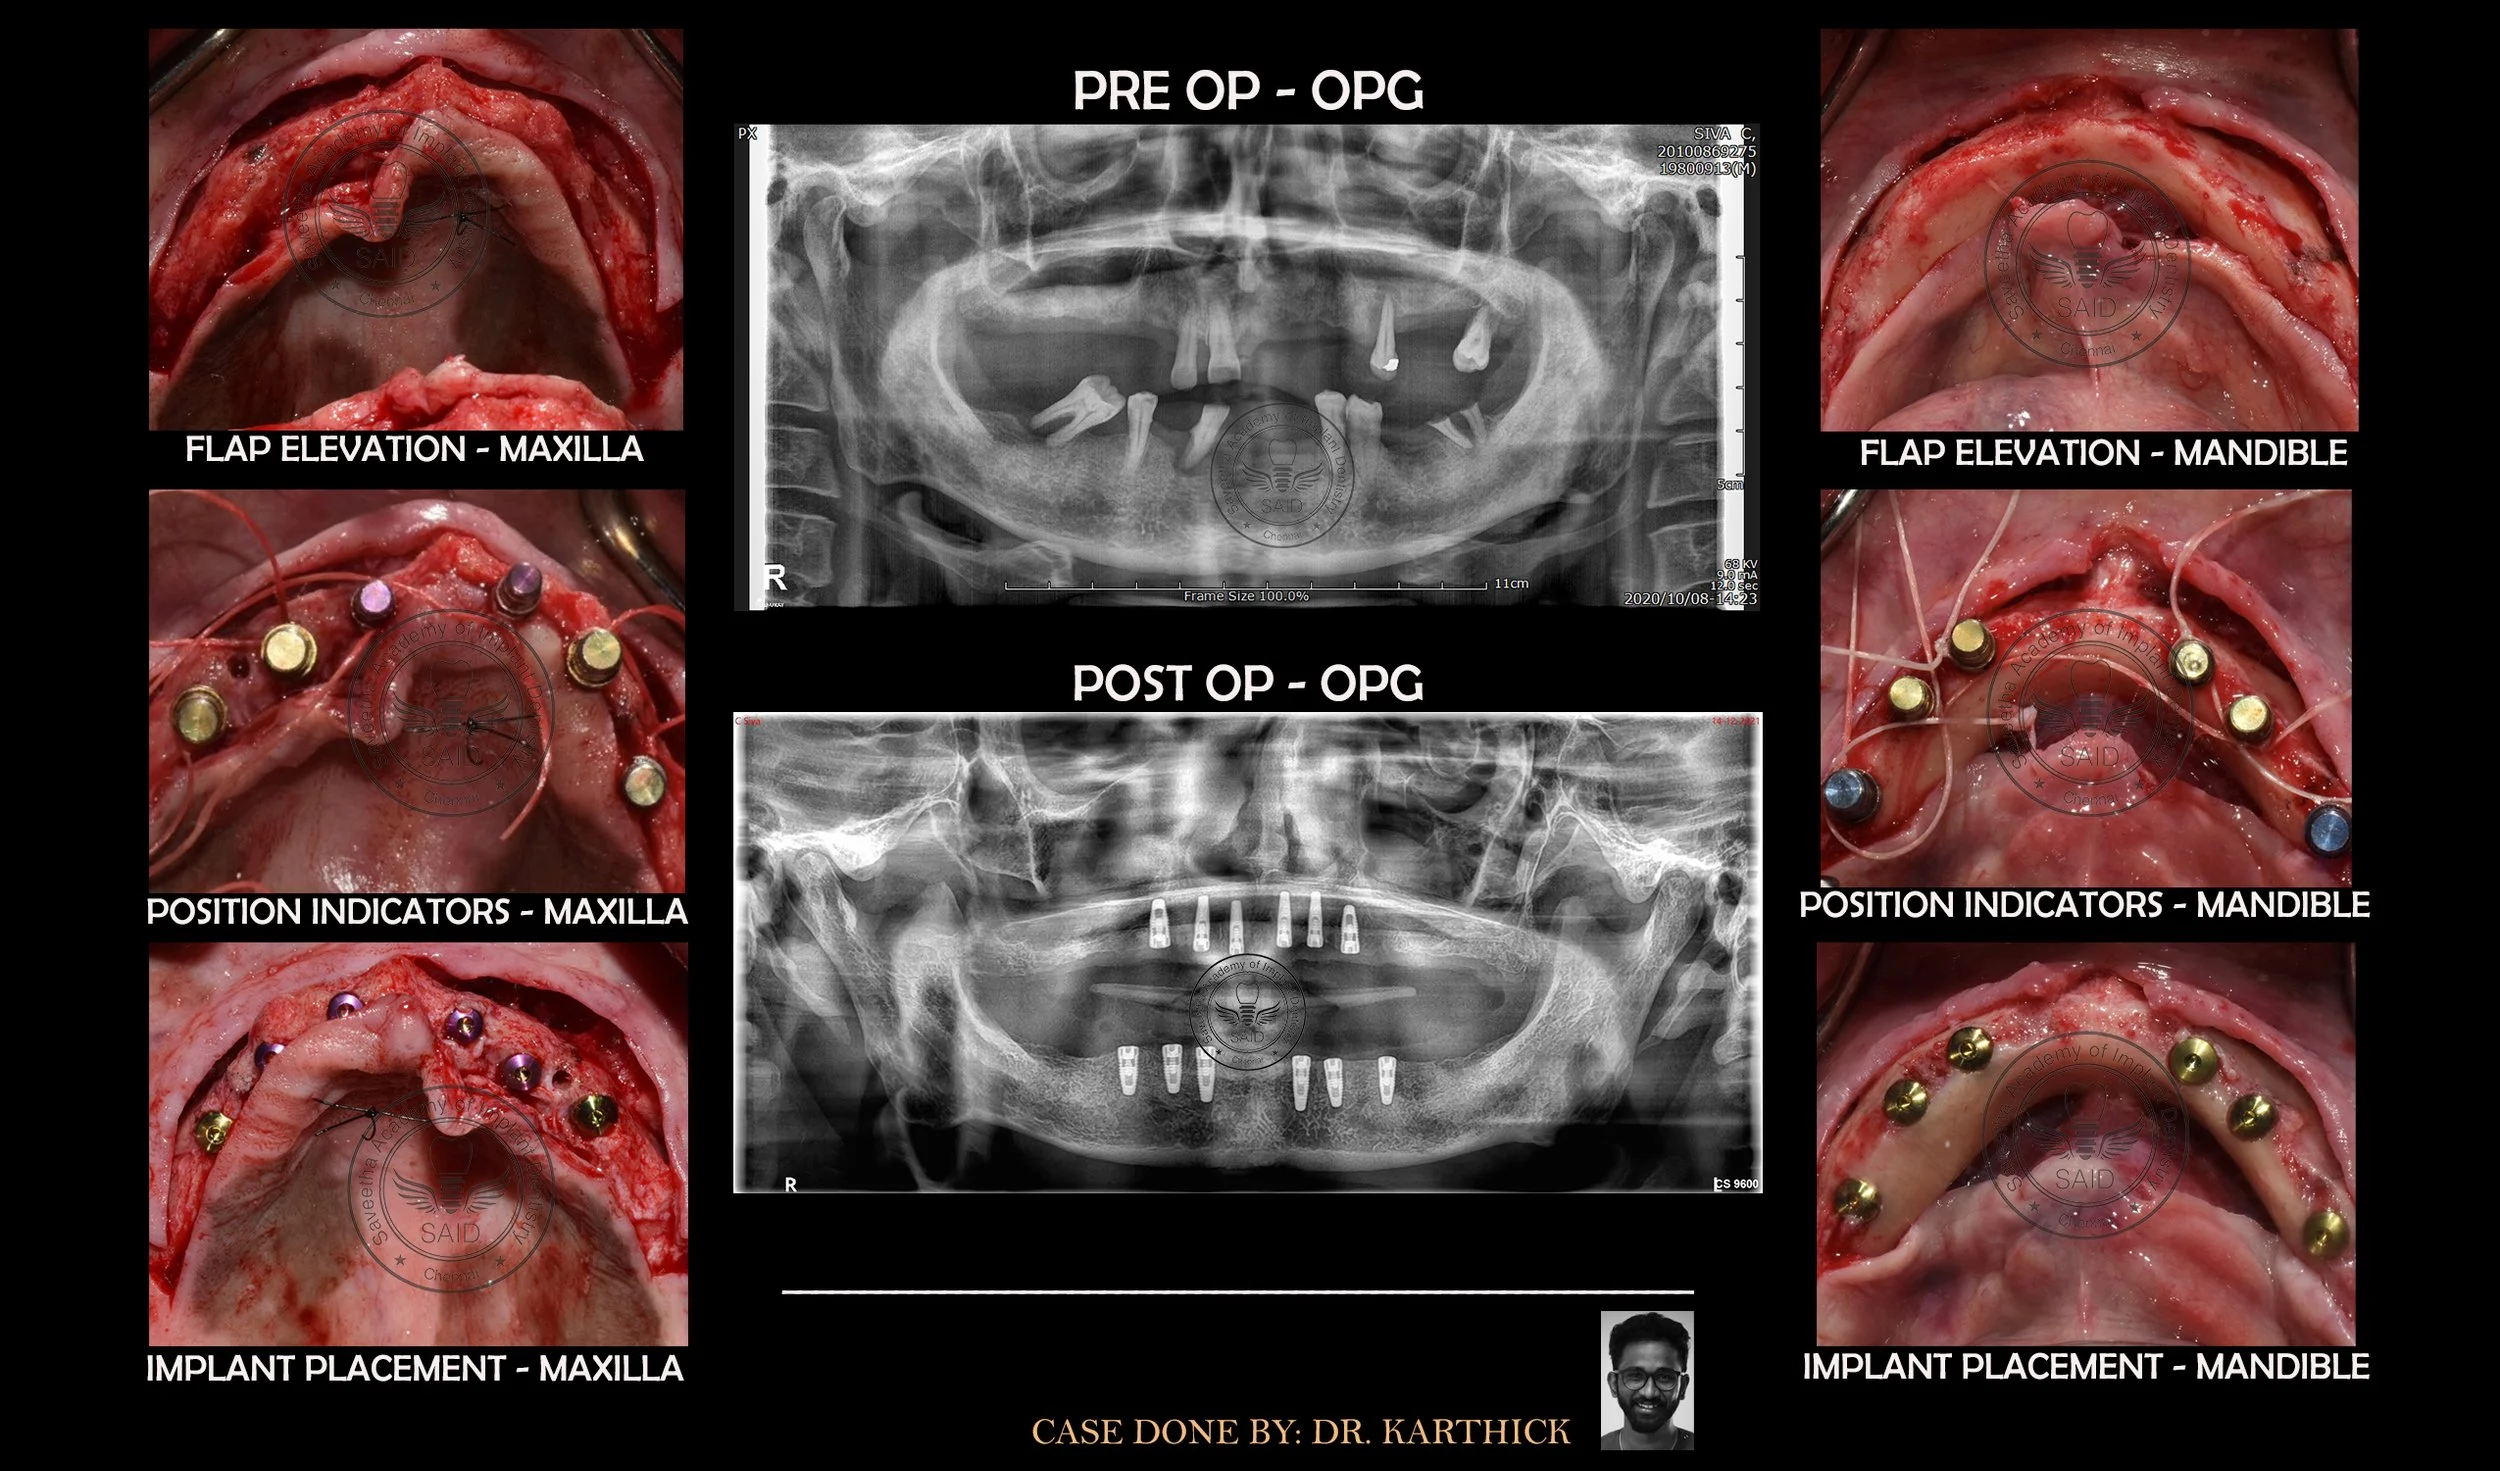

SOCKET PRESERVATION - IMPLANT PLACEMENT

Patient reported having fractured upper front teeth. CBCT evaluation showed defective Incisor. Hence, the teeth was extracted and the socket was preserved using bone grafts material and membrane. After 3 months of adequate healing, Implants were placed.